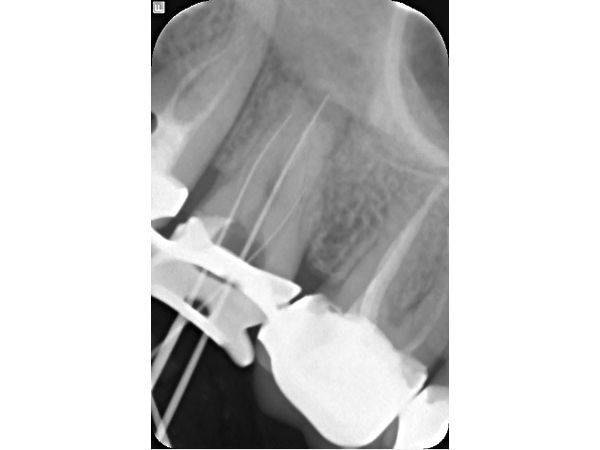

В поликлинике "Наша Клиника-Дент" проведено визиографическое обследование свищевого хода, предварительно в него был введён гуттаперчевый штифт для уточнения локализации воспалительного процесса. Выявлен очаг воспаления в области корней 17 зуба. Также обнаружен участок повышенной плотности, по конфигурации соответствующий фрагменту инструмента в мезиально-щёчном корне 16 зуба.

- Обработка каналов эндодонтическим инструментом Profile: 40.04 (размер 40, конусность 0,4) — щёчные каналы, 45.04 (размер 45, конусность 0,4) — нёбный канал.

Третье посещение. Свищ отсутствует, перкуссия безболезненна. Проведена антисептическая обработка каналов, латеральная конденсация гуттаперчи + AH-plus (методика пломбирования корневых каналов).